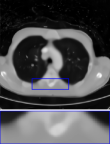

CT We evaluate on computed tomography with Gaussian noise, modeled as , where is the Radon transform. The acquisition uses 51 angles, i.e., about of the LIDC-IDRI image width, with as in training. Results are reported in the rightmost column of Table 2 and visuals in Figure 8. DPIR results are omitted due to instability on this task. The proposed RAM model produces reconstructions with finer details than uDPIR-tied.

CT

We provide in Figure 8 visual results for computed tomography for the in-distribution setup on the top row (i.e., with a setup similar to that of training), and the out-of-distribution setup on the bottom row. In the latter case, measurements are degraded with additional Poisson noise, unlike the training setup.

| uDPIR tied | RAM | Ground-truth | ||

| Gaussian CT | ![]() |

![]() |

| 0.607 | 0.642 | SSIM | ||

| Poisson CT | ![]() |

| 0.828 | 0.671 | SSIM |